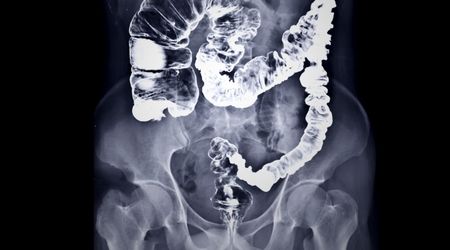

Lynch sendromu, kalıtsal bir kanser sendromudur. Ağrılı kolorektal sendrom olarak da bilinir. Kalın bağırsak ve rahim kanserleriyle yakından ilişkilidir. Özellikle genç yaşlarda gelişir. Genetik mutasyonlara bağlı olarak ortaya çıkan bu durum, aile bireylerinde kansere yakalanma riskini önemli ölçüde artırır. Özellikle 50 yaşından önce teşhis edilen kolon veya endometriyal kanserlerde lynch sendromu akla gelmelidir. Hastalığın erken teşhisi ve düzenli tarama yöntemleri sayesinde, kanser gelişimi önlenebilir veya geciktirilebilir.

Lynch sendromu, genetik geçişli bir kanser sendromudur. Ağrılı kolorektal sendrom olarak da bilinir. En sık olarak kolorektal kanseri ile ilişkilidir, ancak rahim, yumurtalık, mide, ince bağırsak, karaciğer, idrar yolları ve beyin tümörleri gibi çeşitli kanser türlerine yakalanma riskini de artırır. DNA onarım genlerinde meydana gelen kalıtsal mutasyonlar nedeniyle, hücreler hasarlı DNA’ları düzeltemez ve bu da kanser oluşumuna yol açabilir.